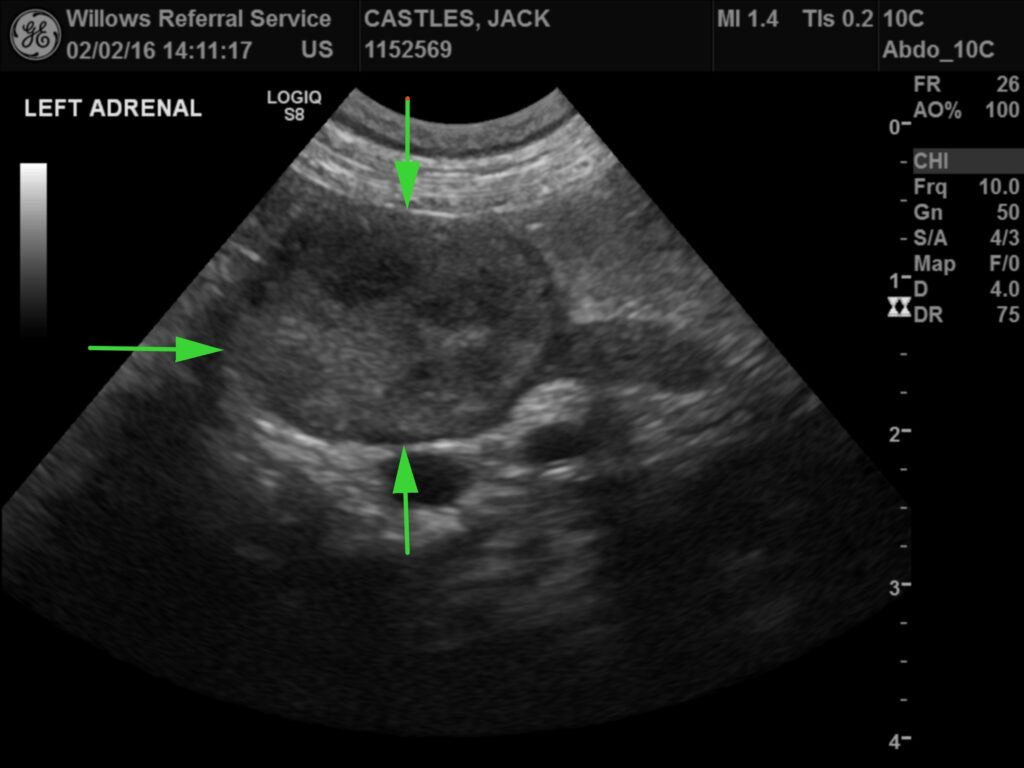

Diagnosis of HAC requires a full history, detailed physical examination, routine blood, urine tests and hormone tests. Diagnostic imaging such as an ultrasound scan of the abdomen (image 1) or a CT scan of the abdomen or brain (image 2) are required to help confirm the diagnosis or differentiate between PDH and ADH. HAC can be very hard to diagnose as the disease can have similar symptoms to other diseases and hormone test results can be falsely positive with some of these other diseases mimicking HAC. Falsely negative hormone results can also occur in some dogs with HAC.

Fig 1: Abdominal ultrasound scan showing an adrenal gland mass